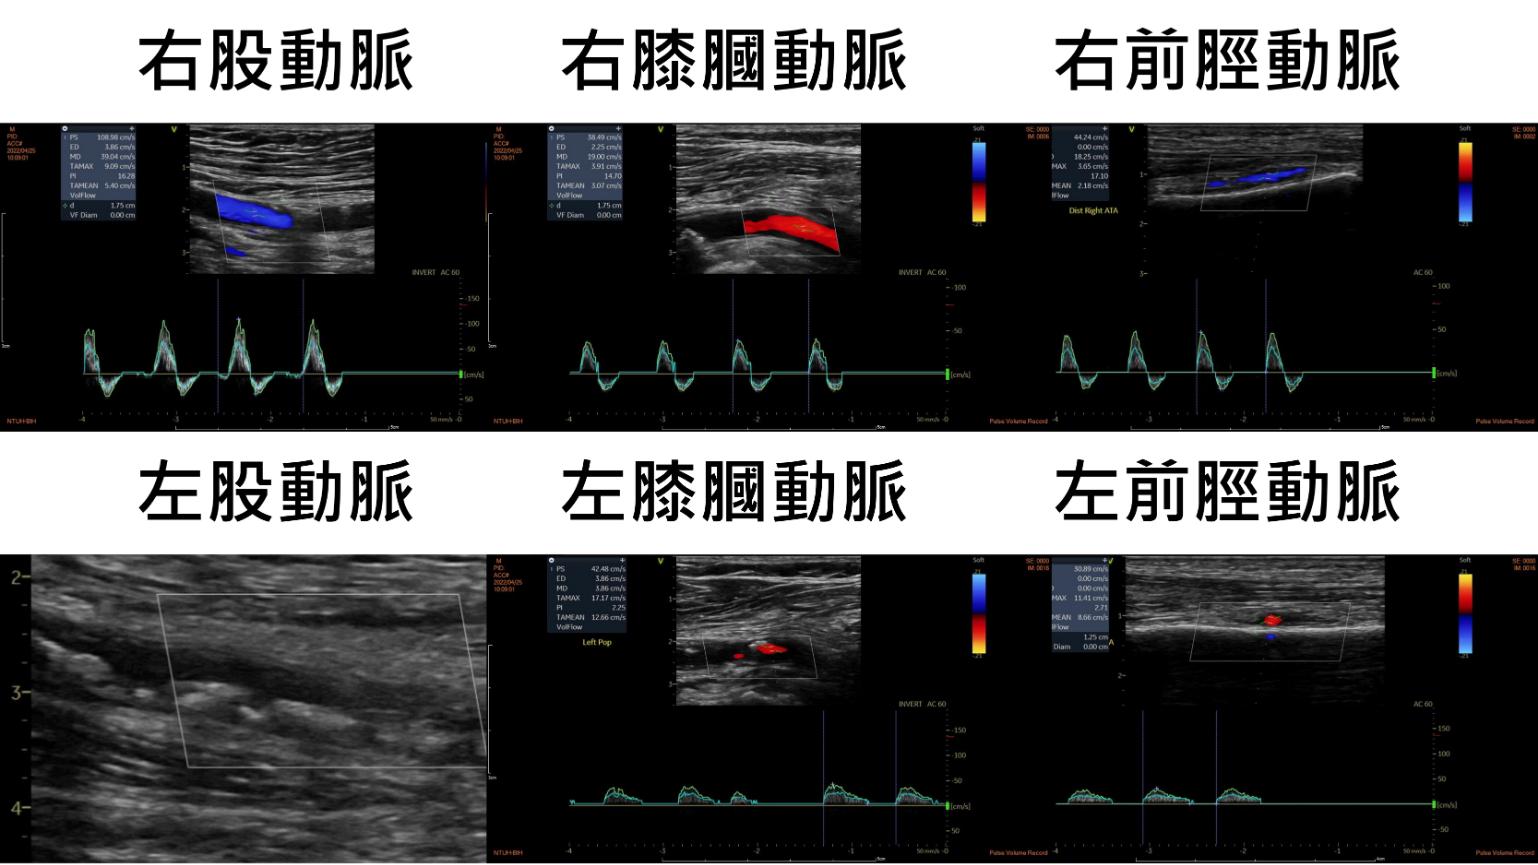

林醫師聽完覺得不尋常,伸手檢查陳大哥足部的脈搏,發現右腳脈搏強而有力,左腳卻摸不到。接著安排了下肢動脈超音波檢查,證實左腿股動脈全阻塞(圖一),而右腿的血流則完全正常。